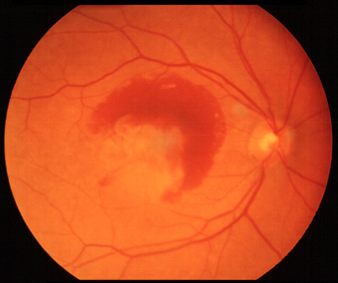

Le alterazioni sopra descritte rappresentano una situazione di rischio perché si sviluppino al di sotto della retina dei nuovi vasi sanguigni (neovasi) con l’intento di portare nuovi nutrienti e nuovo ossigeno alla retina in difficoltà. Questi neovasi però sono alla base dell’evoluzione umida (neovascolare) della DMS poiché avendo pareti fenestrate (non continenti) perdono liquidi e/o sangue e infiltrandosi nello spessore della retina ne distruggono l’architettura. Rispetto alla forma secca il processo neovascolare-essudativo è rapidamente ingravescente e si conclude con la formazione di un’ampia cicatrice maculare in cui i fotorecettori risultano distrutti. A questo punto la visione centrale è gravemente e irrimediabilmente compromessa. La forma umida è responsabile dell’80% dei casi di cecità legale da degenerazione maculare.

A sinistra e al centro: forma umida della degenerazione maculare senile con emorragia maculare. A destra: stadio finale con cicatrizzazione della macula (maculopatia disciforme)